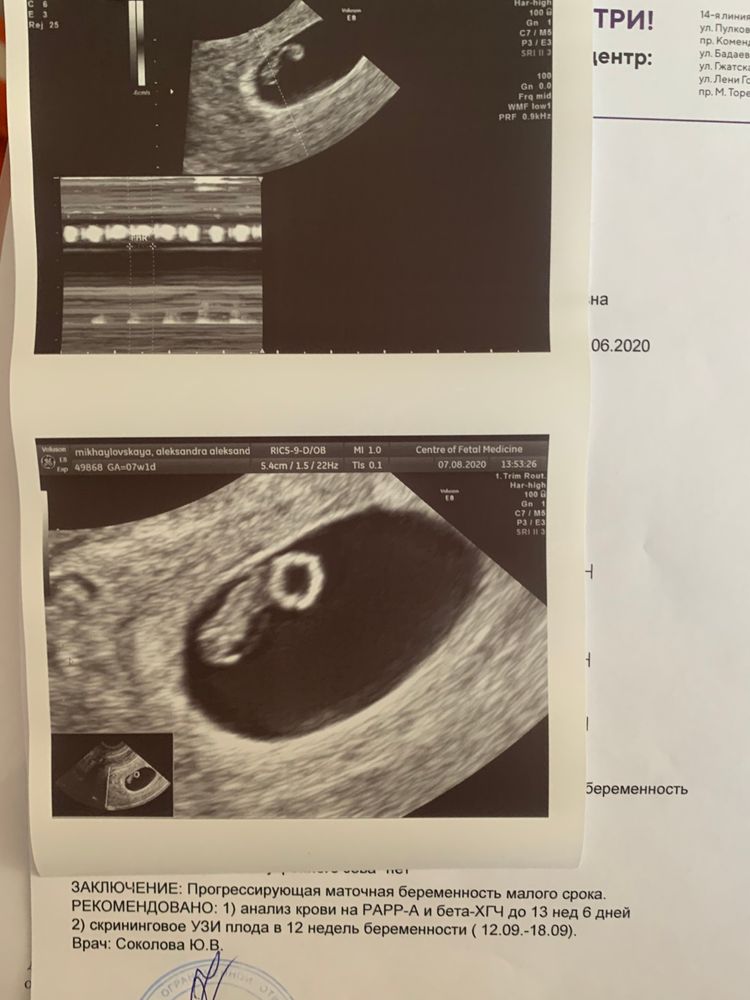

Фотографии на ранних этапах беременности

Раздел: Визуальный дайджест